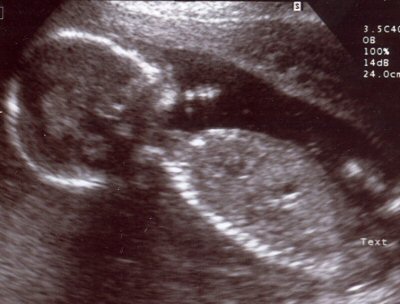

A hospital sonogram image of a human child in its mother's womb soon to be born.